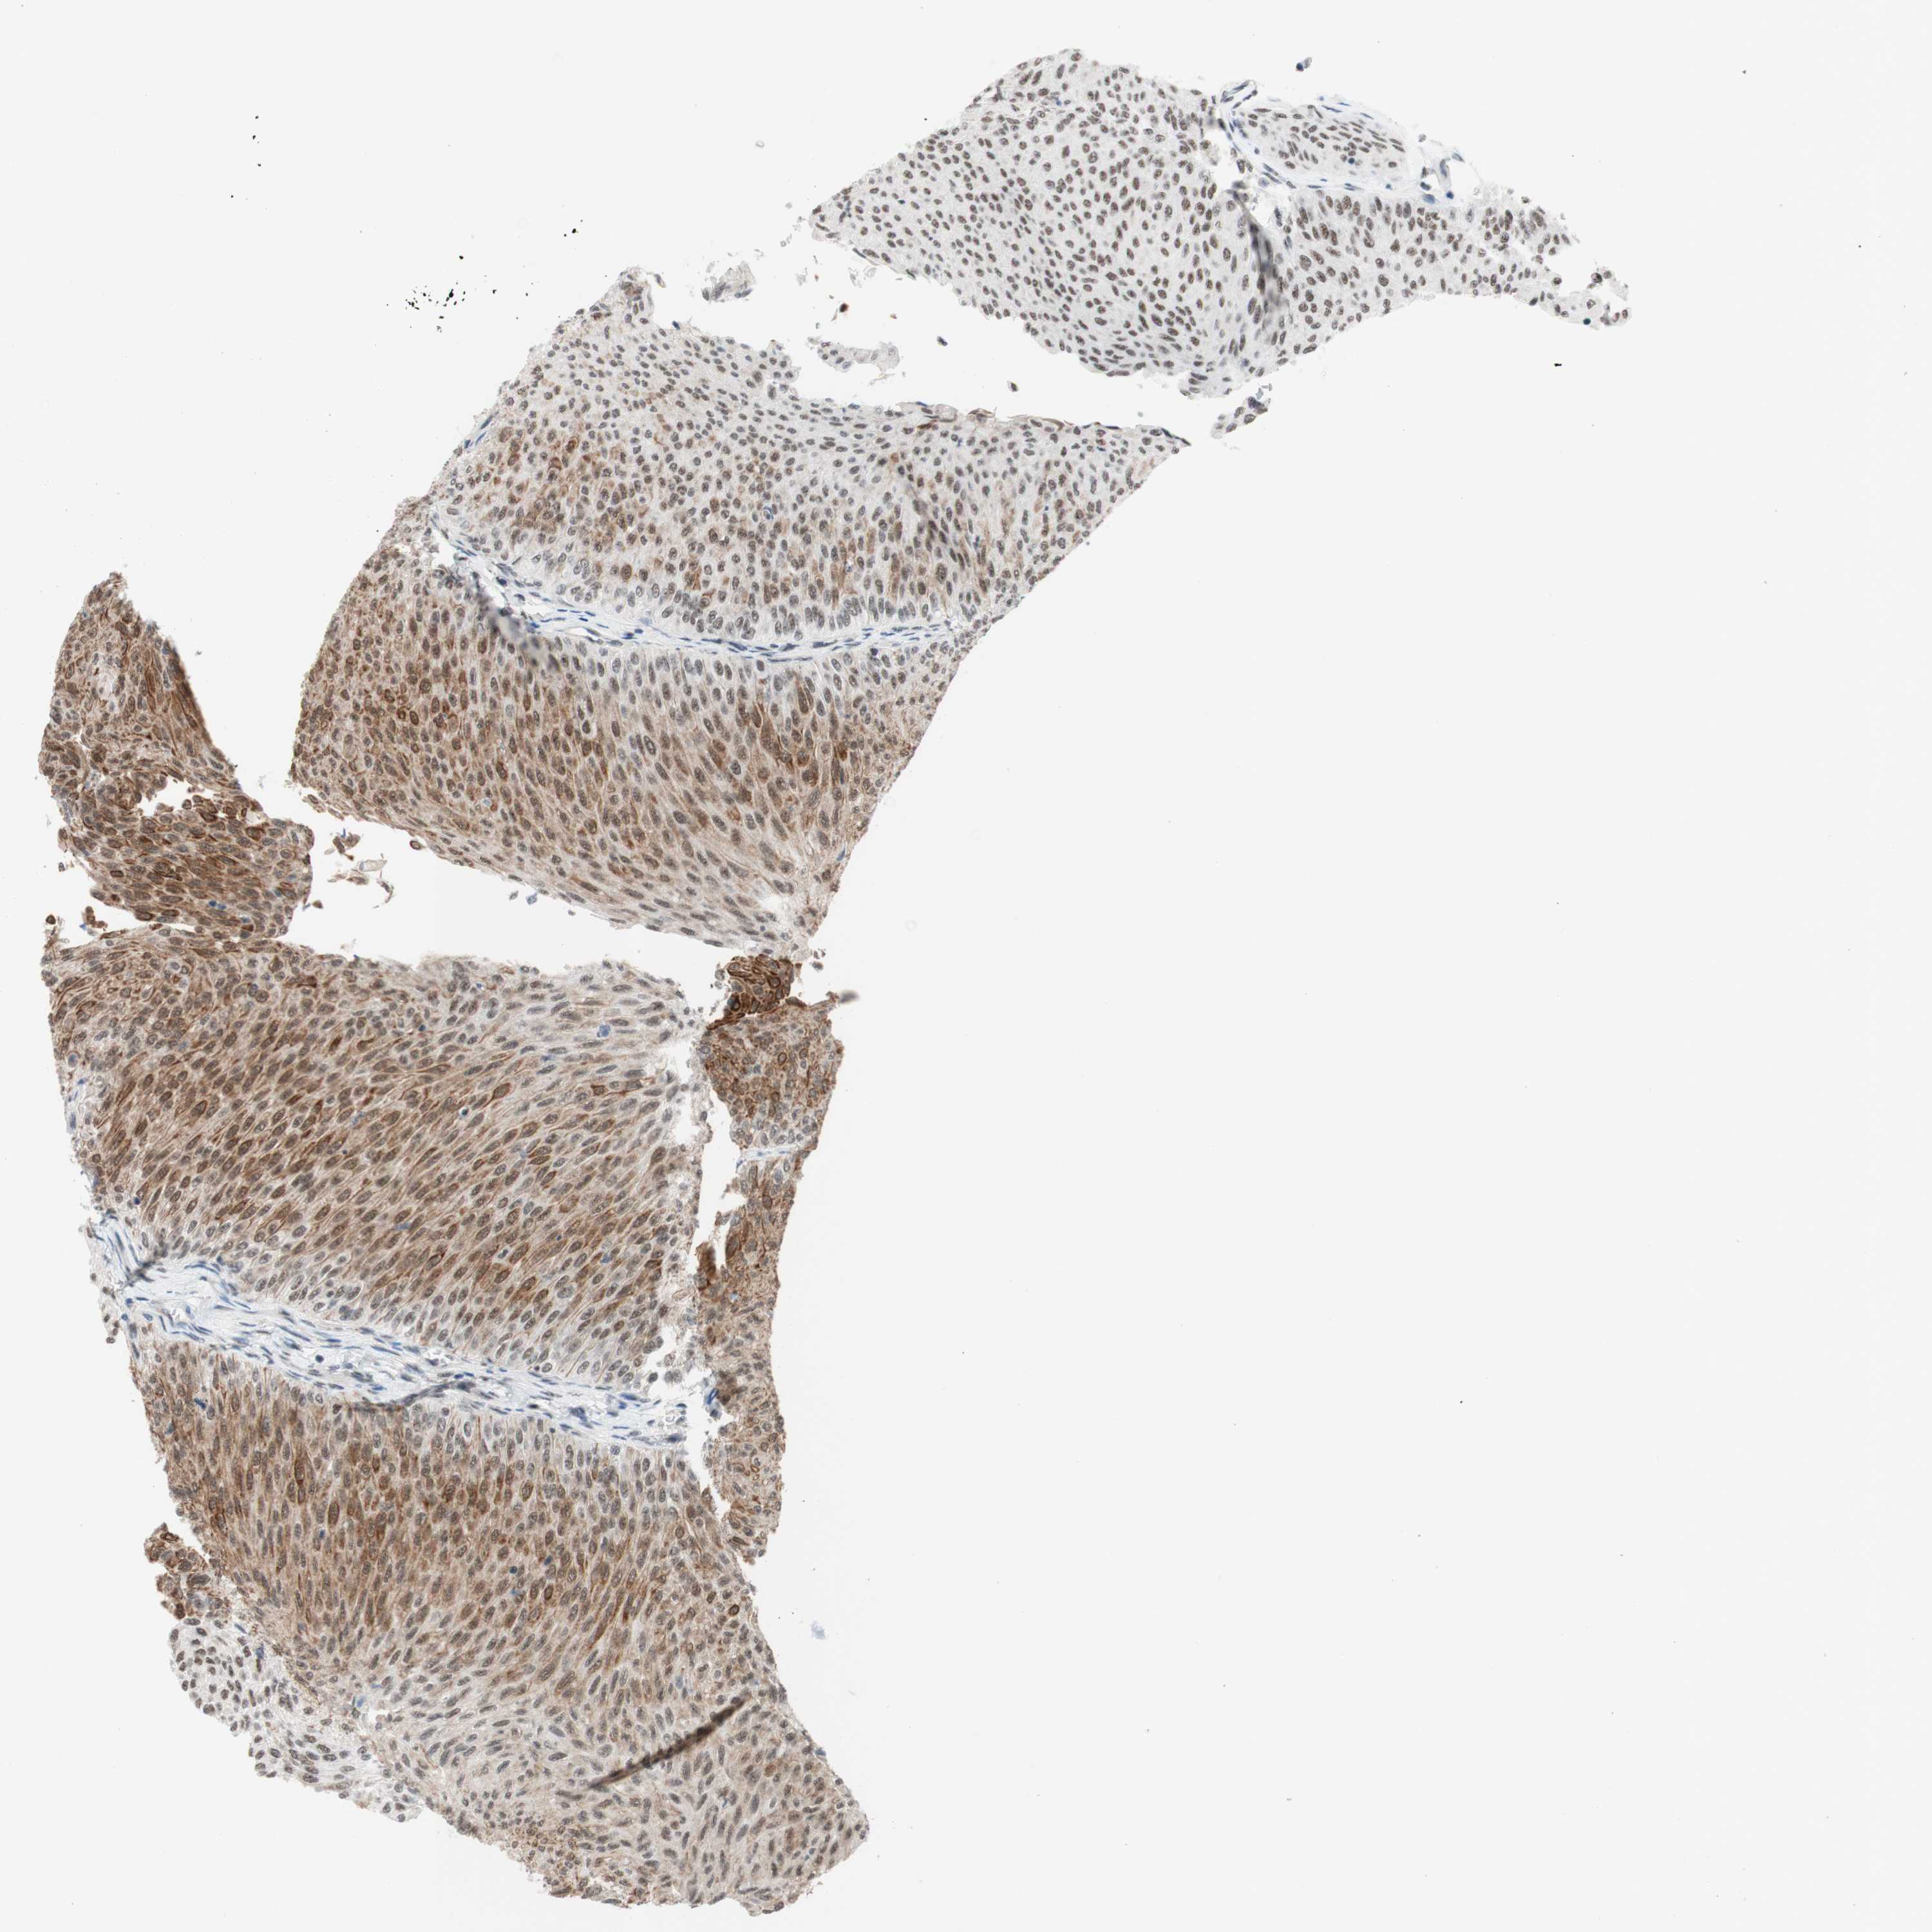

UROTHELIAL CANCER - Protein expressioni

A mouse-over function shows sample information and annotation data. Click on an image to view it in a full screen mode. Samples can be filtered based on level of antibody staining by selecting one or several of the following categories: high, medium, low and not detected. The assay and annotation is described here.

Note that samples used for immunohistochemistry by the Human Protein Atlas do not correspond to samples in the TCGA dataset.

Antibody stainingi

Antibody staining in the annotated cell types in the current human tissue is reported as not detected, low, medium, or high, based on conventional immunohistochemistry profiling in selected tissues. This score is based on the combination of the staining intensity and fraction of stained cells.

Each image is clickable and will lead to virtual microscopy that enables deeper exploration of all samples and also displays staining intensity scores, fraction scores and subcellular localization as well as patient and tissue information for each sample.

Antibody HPA038051

Antibody HPA059070

Antibody CAB012448

Staining

High

Medium

Low

Not detected

Intensity

Strong

Moderate

Weak

Negative

Quantity

>75%

75%-25%

<25%

None

Location

Nuclear

Cytoplasmic/membranous

Cytoplasmic/membranous,nuclear

Urothelial carcinoma, High grade

Urothelial carcinoma, Low grade

Urothelial carcinoma, NOS